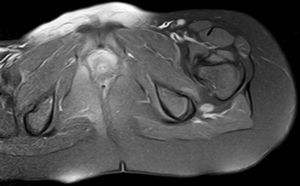

Como pruebas complementarias se realizaron radiografías de caderas, pie y pierna izquierda; ecografía de hueco poplíteo y tercio proximal de miembro inferior izquierdo que descartó trombosis venosa; analítica de sangre completa con estudio de coagulación, autoinmunidad y CPK normales. El electroneurograma y electromiograma objetivaron signos compatibles con la existencia de una mononeuropatía axonal parcial (axonotmesis) del nervio ciático común izquierdo con afectación predominante del componente peroneo. Se completa estudio con resonancia magnética (RM) de columna lumbosacra y estudio RM pélvico y de miembro inferior donde se identificó una lesión de partes blandas bien definida en el teórico trayecto del nervio ciático izquierdo, visible desde el nivel de la escotadura ciática hasta caudalmente el hueco poplíteo, compatible con neurofibroma. (figs. 1 y 2)

Los neurofibromas plexiformes son tumores que afectan a las estructuras del nervio (plexo, fascículos o ramas nerviosas)3. Se calcula que su incidencia es de alrededor de un 17% en NF tipo 12. El estudio de imagen para detección y caracterización se realiza mediante RM, generalmente explorando los 3 planos del espacio con secuencias T1, T2 supresión de grasa y estudio T1 supresión de grasa tras gadolinio intravenoso. De forma habitual los neurofibromas son hiperintensos en T2, realzan tras contraste intravenoso, se relacionan anatómicamente con un nervio y pueden mostrar característicamente un «patrón en diana»3–6. El 12% de estas lesiones presentan degeneración maligna; generalmente muestran un crecimiento rápido o un dolor mantenido. Los estudios con tomografía de positrones podrían ser útiles en el estudio de estas lesiones ante la sospecha de malignización, encontrando en algunos estudios una sensibilidad de hasta el 90% con una especificidad del 87% (Warbey 2009),7-9. El tratamiento de las lesiones sintomáticas y/o malignas se basa en la cirugía. La quimioterapia y radioterapia se reservan en caso de malignización. Dada la naturaleza vascular de estas lesiones también se han utilizado inhibidores de la angiogénesis o inductores de la diferenciación celular10.